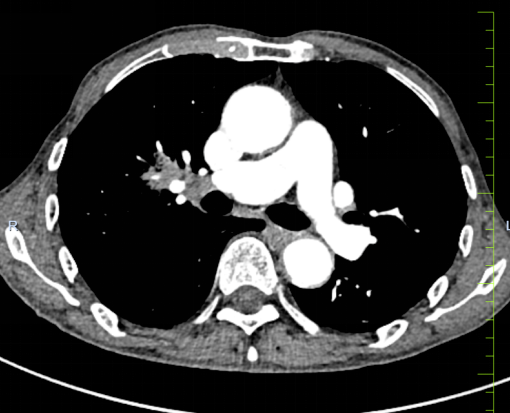

此次接受穿刺的患者已是高龄,检查后发现,患者右肺存在明确占位性病灶,且病灶周边血管分支异常密集,属于典型的富血供病灶。这一特殊病灶情况,给穿刺操作带来极大隐患:穿刺针尖只要出现微小偏差,就极易刺破周边血管,引发大出血、血气胸等严重并发症,甚至直接危及患者生命,堪称临床穿刺的“高危禁区”。

术前,团队借助增强CT三维重建,精细分析病灶与周围血管、胸膜的关系,规划最优穿刺路径,并设定进针角度、深度与速度。针对患者高龄易紧张的特点,医护人员还进行一对一呼吸训练,帮助其平稳配合。

手术当日,在CT精准定位下,穿刺针一次性抵达病灶核心,成功获取足量病理组织,术中无渗血、无血管损伤。术后复查CT显示无出血、气胸等并发症,患者全程清醒,生命体征平稳。